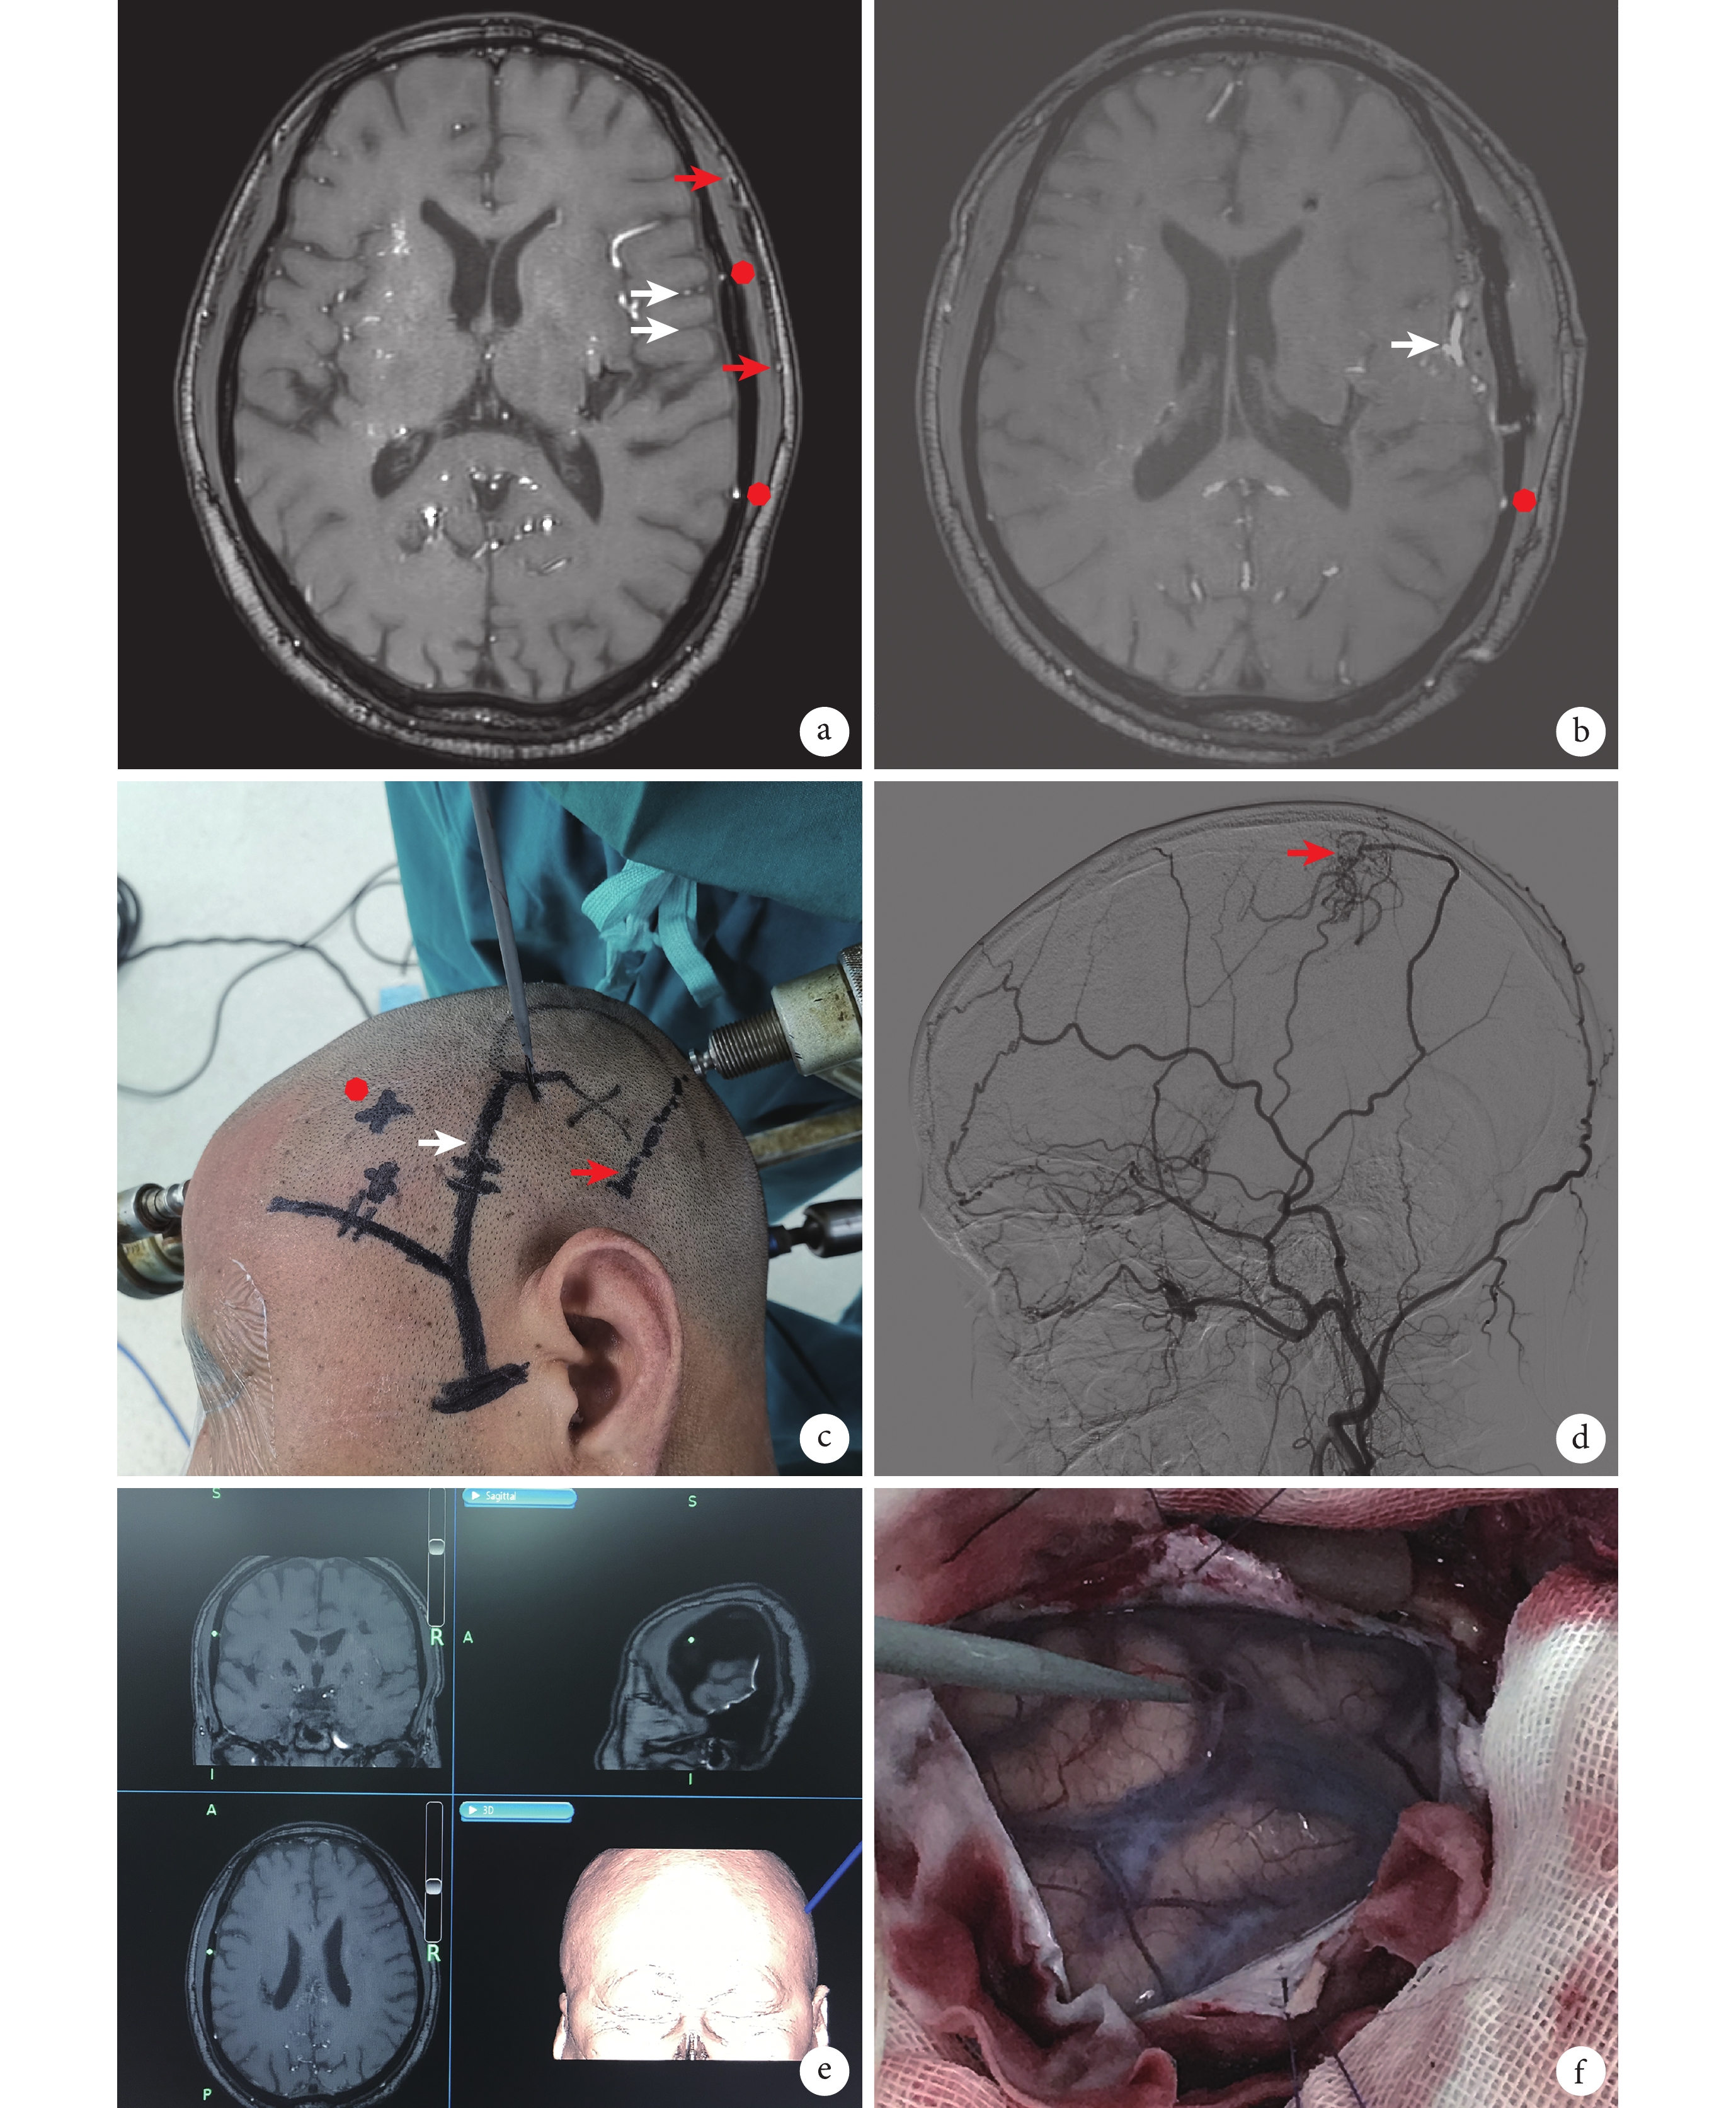

a. 術前 TOF-MRA 圖像,白箭指示皮質動脈,紅色圓指示腦膜中動脈前、后支,紅箭指示顳淺動脈前、后支;b. 術后 TOF-MRA 圖像,白箭指示吻合口,紅色圓指示腦膜中動脈后支(術前有代償,得以保留);c. 根據導航設計手術切口,白箭(頭部黑色實線)指示顳淺動脈,紅箭(頭部黑色虛線)指示腦膜中動脈后支,紅色圓(頭部黑色叉)指示可能的淺表受體動脈;d. 術前頸外動脈造影圖像,紅箭指示腦膜中動脈后支向顱內代償;e. 患者術中導航圖,圖中亮點指示為術中驗證受體血管位置;f. 患者術中照片,導航棒指示實際受體血管位置

所有患者術前完善 TOF-MRA 序列檢查,手術由同一位高年資神經外科醫師完成,術后 1 周復查 TOF-MRA 序列進行再評估。所有入組患者的術前評估方法一致,均以基于腦血管造影、頭顱 CT 灌注、頭顱 MRI 等影像學檢查的綜合評估為主。本研究主要利用 TOF-MRA 序列在術前評估供體血管、受體血管、腦膜中動脈,從而指導手術切口設計(圖1)。根據術中是否使用導航技術,將患者分為導航組和對照組。其中導航組術中使用導航儀輔助。

導航技術已被廣泛用于神經外科手術[15],可將 TOF-MRA 原始圖像數據導入 Medtronic 導航儀進行實時導航,直接給予手術指導。術中可根據導航,精準定位顳淺動脈、已經產生代償的腦膜中動脈以及合適的淺表受體血管(圖1),從而更合理地設計出手術切口及骨窗,達到避免損傷已有代償的同時,更快速、精準地完成搭橋手術。

① 顳淺動脈評估:TOF-MRA 三維重建可以清楚地看到顳淺動脈前后支,對比數字減影血管造影具有高度一致性。在薄層 TOF-MRA 中可以在皮膚與顳肌之間清楚地找到顳淺動脈前后支(圖1a)。導航組在術中導航時,可以用導航針標記顳淺動脈走行,發現與手觸定位具有一致性。

② 硬腦膜血管評估:首先由腦血管造影評估硬腦膜血管是否產生顱內代償(圖1d),TOF-MRA 薄層掃描找到對應的硬腦膜血管以及產生顱內代償的顱內外吻合處。

③ 受體血管評估:數字減影血管造影往往無法評估大腦皮質的受體血管,而薄層 TOF-MRA 有腦組織參照,可以清楚顯示皮質動靜脈,并指導受體血管的選擇。皮質靜脈相對較粗且表淺,皮質動脈相對較細且多位于腦溝內(圖1a)。

所有病例均在術后 1 周復查 TOF-MRA,評估吻合口的通暢情況,同時通過顯示的受體動脈與術前磁共振血管成像作對比(圖1b),來驗證術前對該受體血管判斷的準確性。此外,還通過結合 MRI 其他序列作更為詳盡的評估。